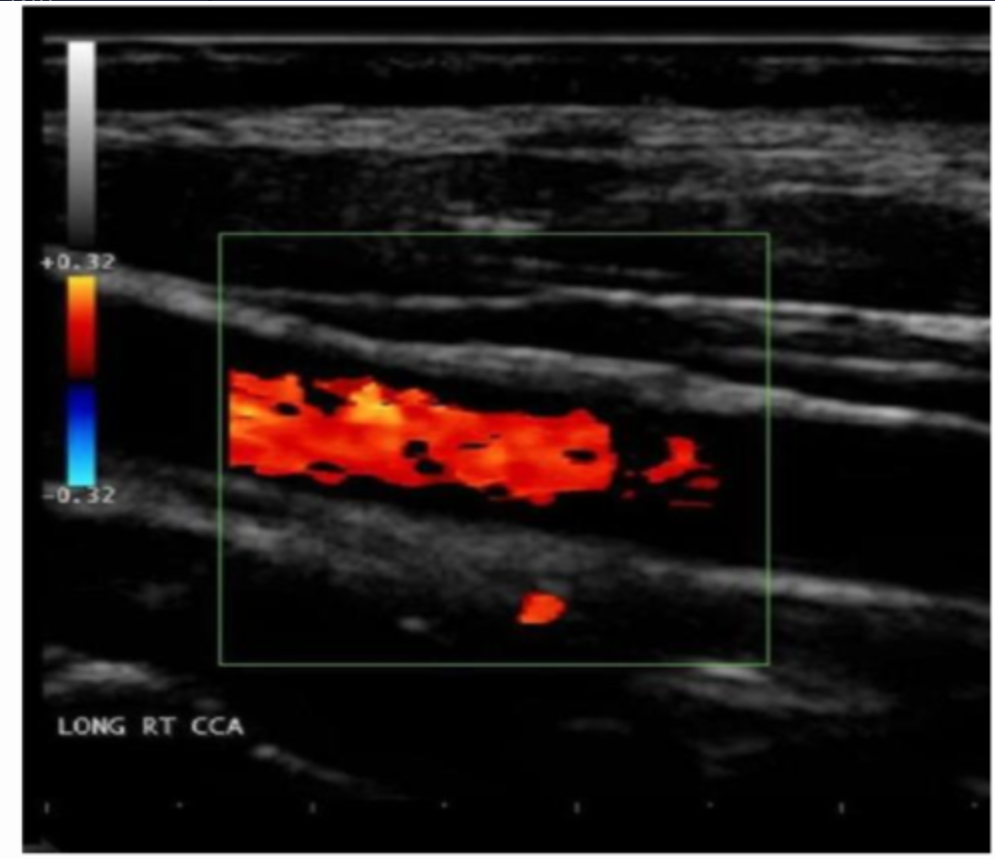

Which of the following correctly describes the color displayed on the image?

a. the color scale should be reduce so that the entire vessel is filled with red color

b. the heel-to-toe method can be used to change the course of the vessel across the image and this will allow the vessel to accurately display a single color

c. the color scale should be reduced so that the entire vessel is filled with blue color

d. the red and blue color indicate that flow is moving in two different directions simultaneously in the vessel

the heel-to-toe method can be used to change the course of the vessel across the image and this will allow the vessel to accurately display a single color